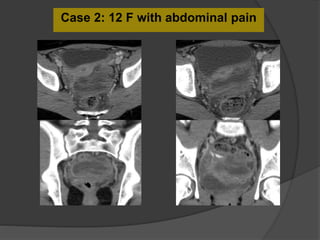

Case 2: 12 F with abdominal pain

Case 2: 12 year old female with abdominal pain

Dilated fallopian tube with thickened and enhancing tubal wall

Right

ovary

Complex

tubular

mass

Follow-up US

Diagnosis: Torsion of the left Fallopian tube

Dilated tube with thickened, echogenic walls

and absence of vascular flow in the tube

Isolated torsion of the fallopian

tube

 Rare cause of lower quadrant pain primarily affecting

adolescents and ovulating women. Risk factors:PID,

tubal ligation, neoplasm, adhesions, gravid uterus and

trauma.

 Complications include fallopian tube necrosis, an

increased risk for superinfection and peritonitis. Local

necrosis can also result in irreversible damage to the

ipsilateral ovary.

 Treatment options include surgical detorsion,

salpingotomy, and salpingectomy depending on the stage

of intervention and presence of complications.